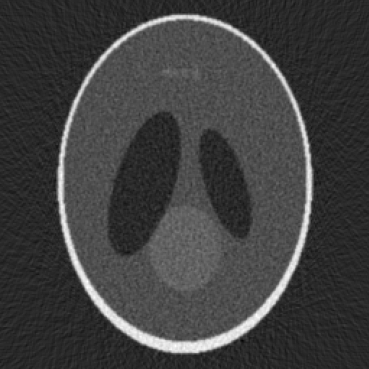

(b) Jitter

(c) Poisson Noise

Figure 1: Visualization of simulated artifacts with Shepp Logan Phantom.

The framework now includes advanced tools for simulating realistic imaging artifacts. These include features such as detector jitter, Poisson noise, Gaussian noise, ring artifacts, and gantry motion blur. The ability to simulate such artifacts enables the training and validation of deep learning models under realistic imaging conditions, leading to more robust and generalizable reconstructions. These tools also allow researchers to explore the impact of different types of noise and artifacts on reconstruction quality in a controlled environment.

Detector jitter represents a misalignment in detector readings caused by slight mechanical or electronic fluctuations. In software, random pixel shifts are introduced for each detector column or row to replicate this misalignment. This process can highlight the sensitivity of a reconstruction algorithm to geometric variations.

Poisson noise arises from the discrete nature of photon counting. Each pixel value in the sinogram is used as a rate parameter for the Poisson process, which approximates the randomness of detected X-ray photons. This addition of noise is especially important for low-dose simulations, since quantum fluctuations are more noticeable at reduced intensities.